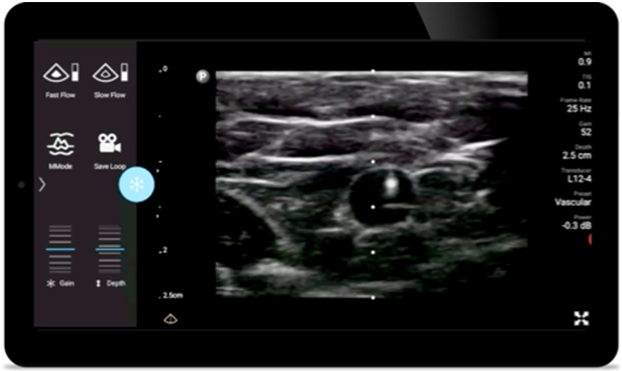

Lumify handheld ultrasound for anesthesiology helps you clearly visualize border definition with your needle placement, surrounding nerves, vessels and fascial planes.

Lumify helps you clearly visualize needle placement, surrounding nerves, vessels and fascial planes.

Lumify L12-4 broadband linear array transducer

• 12 to 4 MHz extended operating frequency range

• Aperture size: 34mm

• 2D, steerable color Doppler, M-mode, advancedXRES and multivariate harmonic imaging, SonoCT

• High resolution imaging for shallow applications: soft tissue, vascular, superficial, musculoskeletal and lung

• Center line marker

• USB-C transducer with replaceable cable